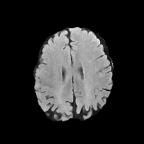

Brats MRI T1 Scans, FLAIR, Tumors. Lastly, we used a dataset of brain MRI scans [28] with two modalities: T1 (naive) and FLAIR (T2 Fluid Attenuated Inversion Recovery) [15]. We adapt the protocol that Cohen et al. [9] used for the Brats2013 datasets [27] to the more recent Brats2018 [3] dataset by varying the percentage of scans with tumors in the target domain. We selected transverse slices from the to range in the caudocranial direction [1] for both T1 and FLAIR scans. Each scan was classified as tumorous if more than of its pixels were labeled as such, and as healthy if it contained no tumor pixels. The training set contains images from each modality, with all source images (T1) being healthy and the target domain (FLAIR) comprising tumorous scans. The test set contains paired scans of healthy brains.

We adapt the protocol of Cohen et al. [9] from the Brats2013 datasets [27] to the more recent, larger, and more diverse Brats2018 dataset [2]. We consider two MRI modalities: native (T1) and Fluid Attenuated Inversion Recovery (FLAIR). We selected transverse slices from the to range in the caudocranial direction [1] for both modalities of scans.

We label each scan as tumorous if more than of its pixels are labelled as such, and as healthy if it contains no tumor pixels. We only use high-grade gliomas (HGG) instead of low-grade gliomas (LGG) as the are more easily observable [24]. In total, we obtain 5035 pathological pairs and 1135 healthy pairs. The train set is composed of a source domain of T1 images of healthy brains, while the target domain set is composed of FLAIR scans of which (60%) are tumorous and healthy. The test set is composed of aligned scans of healthy brains in both modalities.